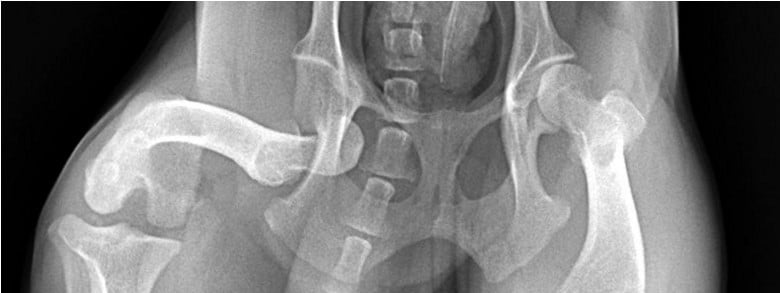

Hip Dislocation (Canine Hip Dislocation)

- It is frequently after trauma

- Leads non-weight-bearing lameness

- Limb is frequently seen shortened and rotated

Dog hip dislocations are among the most common traumatic orthopedic injuries seen by veterinarians in hospital emergency departments.